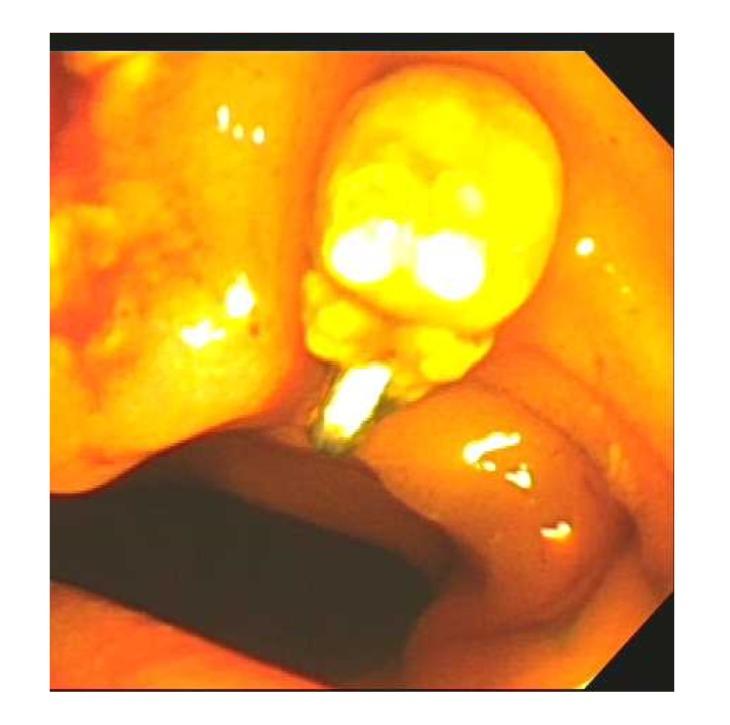

Gallstone disease is a common gastrointestinal pathology that may result in surgical intervention. While cholecystectomy has relatively minimal risks, surgical clip migration is a rare complication that can cause severe morbidity and mortality. This report describes a rare phenomenon of a biliary stone forming onto a migrated surgical clip 14 years after cholecystectomy causing an obstructive jaundice. This case illustrates the importance of keeping a migrated surgical clip on the differential when encountering patients with symptoms of cholangitis after cholecystectomy.

胆结石病是一种常见的胃肠道疾病,可能需要手术干预。虽然胆囊切除术的风险相对较小,但手术夹移位是一种罕见的并发症,可导致严重的发病和死亡。本报告描述了一例罕见现象,即胆囊切除术后14年,一枚移位的手术夹上形成了胆结石,导致梗阻性黄疸。该病例说明了在遇到胆囊切除术后出现胆管炎症状的患者时,将移位的手术夹纳入鉴别诊断的重要性。